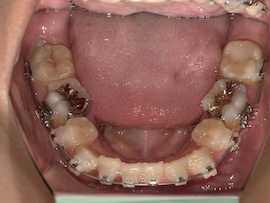

前回から1ヶ月後の歯並びはこんな感じです。